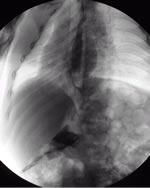

- Deglutogramma e transito esofageo con pasto di bario: evidenzia il passaggio del bolo di mezzo di contrasto dall’orofaringe allo stomaco, e l’eventuale reflusso (Figura 2), mettendo in luce anche alterazioni anatomiche (ernia iatale). Offre inoltre la possibilità di studiare il transito oltre il piloro. Il difetto dell’esame è quello di “fotografare” ciò che accade in “quel momento”, ed in questo senso la sensibilità per RGE è di fatto stimata intorno 50%. Nei bambini portatori di gastrostomia percutanea per via endoscopica (PEG) il contrasto è iniettabile attraverso il “bottone” di gastrostomia (Figura 2 bis).